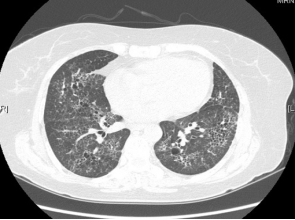

病例:男,62岁,未知抗原,GGO+实变影:

ero为什么不显示叶俏教授:HRCT是发现和鉴别「过敏性肺炎」的重要环节,何种表现指向预后不良?使患者发病的危害因素躲在哪些环境中?_https://www.jmylbn.com_新闻资讯_第42张

病例:女,59岁,鸽子肺,GGO+网格影+囊腔:

ero为什么不显示叶俏教授:HRCT是发现和鉴别「过敏性肺炎」的重要环节,何种表现指向预后不良?使患者发病的危害因素躲在哪些环境中?_https://www.jmylbn.com_新闻资讯_第41张

病例:男,65,饲鸟者肺,GGO+可能UIP型

ero为什么不显示叶俏教授:HRCT是发现和鉴别「过敏性肺炎」的重要环节,何种表现指向预后不良?使患者发病的危害因素躲在哪些环境中?_https://www.jmylbn.com_新闻资讯_第43张